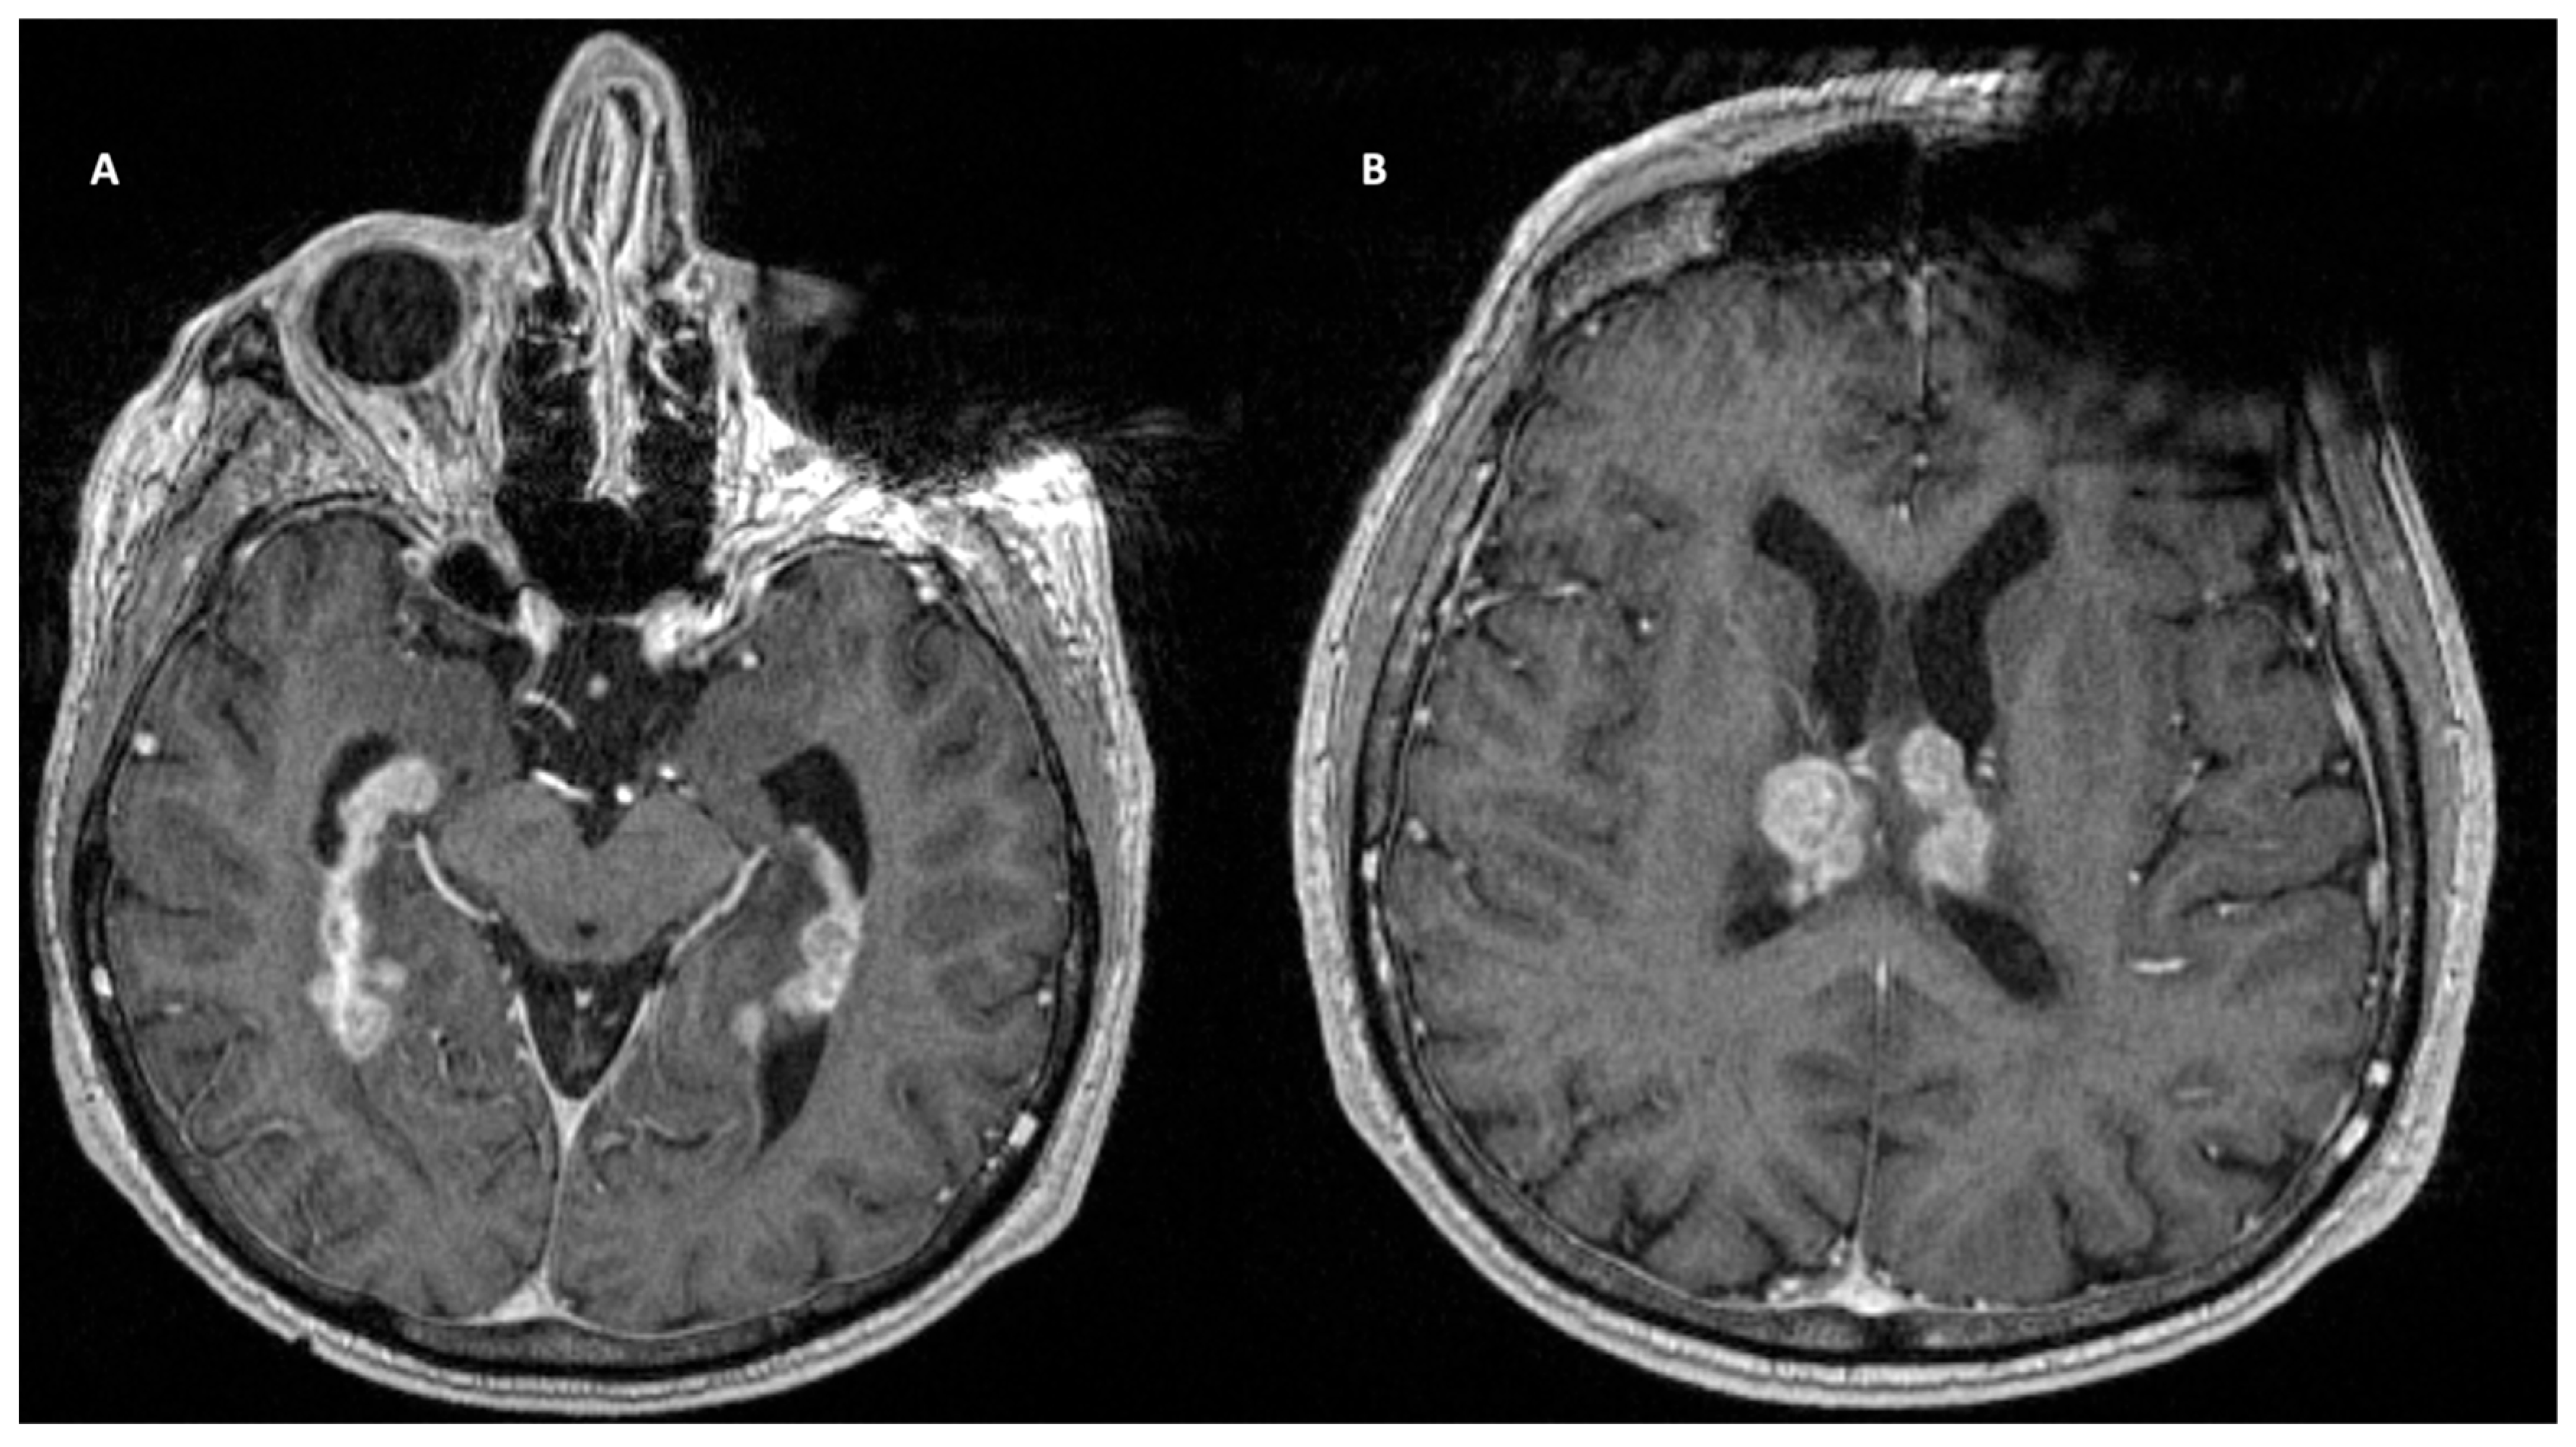

Management primarily consists of surgical management as a mainstay, often coupled with chemoradiotherapy. These approaches generally consist of whole craniospinal irradiation and intrathecal chemotherapy. Radiotherapy, despite its increasing use in pediatric treatment, is still associated with significant long-term consequences and is thus avoided when possible. Long-term sequelae include neurocognitive defects, endocrine dysfunction, growth defects, and an increased risk of a second malignancy. More recently, clinical trials have highlighted anti-angiogenic inhibitors as having promising therapeutic value [92]. Systemic anti-angiogenic treatment with bevacizumab alone and in combination with chemoradiotherapy translated into effective symptom control in five out of nine patients and increased overall survival (Figure 3).

Figure 3.

Targeted bevacizumab therapy for leptomeningeal disease originating from the central nervous system.

Glioblastoma (GBM) has been shown to metastasize to the leptomeninges. Known to spread locally throughout the brain parenchyma, malignant astrocytic tumors are only associated with leptomeningeal spread in 10–21% of cases. Demir and colleagues report the dissemination of a pediatric GBM [93]. Pohar and colleagues describe another metastatic GBM in a 63-year-old female [94]. Spread to the leptomeninges is found to be primarily hematogenous or by direct extension along compact fiber pathways, such as nerves or subependymal regions (Figure 4). In this patient, the tumor infiltrated the lateral ventricle and spread via CSF. On histopathological examination, the tumor was found to be positive for GFAP and vimentin. Studies have linked low GFAP expression with increased leptomeningeal spread [95]. This may indicate that less differentiated astrocytes are implicated in metastasis. An important molecular marker specific to GBM is isocitrate dehydrogenase (IDH). According to WHO, IDH-1 and IDH-2 mutations are found in 10–15% of GBMs. Gliomas expressing IDH-1 wild-type may be associated with leptomeningeal spread. Histone gene mutations are another well-known predictor of leptomeningeal dissemination in GBM. H3K27M mutations are associated with posterior fossa and midline tumors and are associated with leptomeningeal disease and a poor prognosis. The primary management of this tumor is surgical. Gross craniotomies and gross total resections were performed in the aforementioned studies. The standard of care generally involves combination adjunctive chemoradiotherapy. In general, the prognosis is poor, and treatment is palliative. Multiple case reports have identified the leptomeningeal spread of GBM [96,97]. A systematic review showed a median time to spinal metastasis of 10 months and a median overall survival of 3 months following spinal metastasis. Palliative laminectomies have also been performed to ameliorate symptoms. Neither palliative laminectomy, CT, nor RT have demonstrated therapeutic advantage. Interestingly, surgery may have a therapeutic advantage, as those who underwent only a biopsy had a shorter time to develop spinal metastasis [98].

Figure 4.

T1-weighted contrast-enhanced MRI demonstrated a large B-cell lymphoma centered in the subependymal regions of the lateral ventricles.